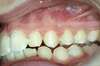

Intra Orale Droite

Intra Orale Face

Intra Orale Gauche